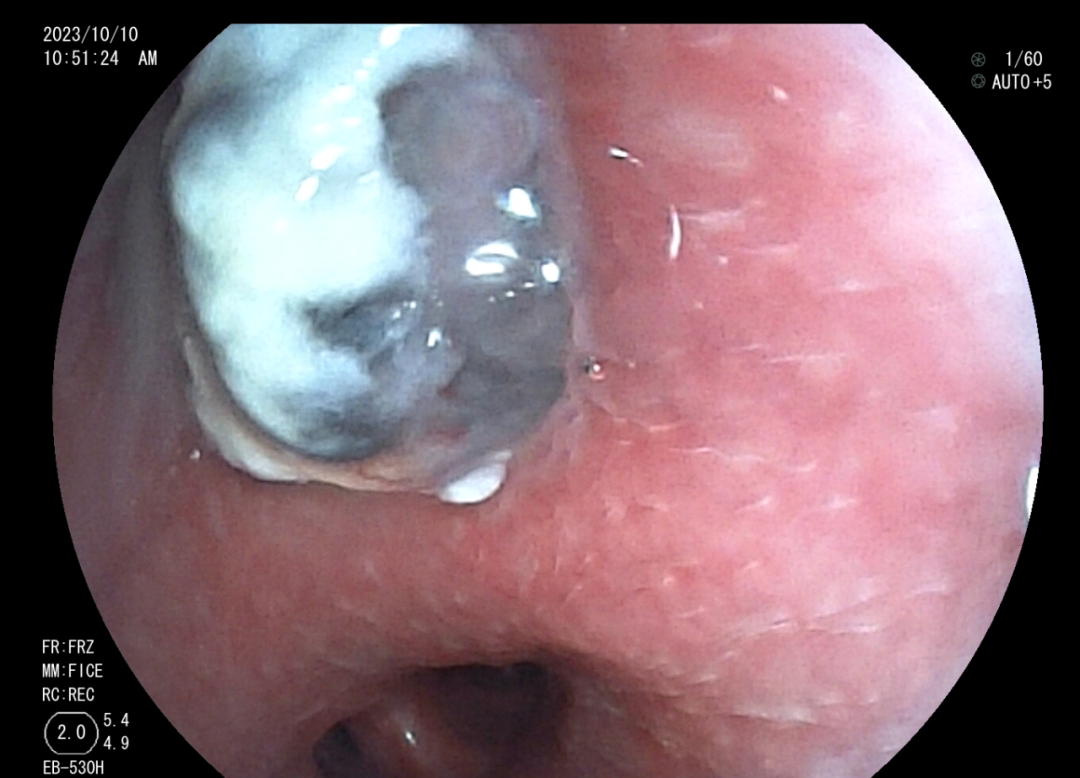

肺科醫(yī)院)住院治療。 10月10日,我院內(nèi)鏡中心為小邰進(jìn)行了第一次支氣管鏡檢查,檢查提示小邰左肺上葉可以看見巨大新生物完全阻塞管腔,充分評(píng)估后,行手術(shù)治療,手術(shù)中應(yīng)用了活檢鉗、異物鉗、冷凍、高頻電刀、內(nèi)鏡下超聲探頭等方法,既保證了患者的安全,又達(dá)到了治療目的,通過三次手術(shù),終于將左上葉巨大腫塊清除掉了。術(shù)后1周復(fù)查胸部CT小邰左肺上葉復(fù)張開來,感覺胸悶、氣促癥狀明顯改善,患者家屬和內(nèi)鏡中心的醫(yī)護(hù)人員由衷為他感到開心。 左上葉巨大新生物阻塞管腔 治療后左上葉恢復(fù)通暢 高頻電消融治療 支氣管結(jié)核科普知識(shí) 在日常生活中大家可能經(jīng)常聽說肺結(jié)核,可是又有多少人知道支氣管結(jié)核呢?其實(shí)支氣管結(jié)核是肺結(jié)核的一種特殊類型,支氣管結(jié)核起病緩慢,癥狀隱匿,缺乏特異性,主要表現(xiàn)為間斷咳嗽、咳痰等。因?yàn)榍捌诎Y狀不重,往往被患者所忽視,等病變逐漸增大,阻塞氣管、支氣管時(shí)可出現(xiàn)嚴(yán)重的呼吸困難、咯血、胸痛等癥狀,嚴(yán)重氣道狹窄甚至可能危及生命。支氣管結(jié)核的診斷需要行支氣管鏡的檢查來發(fā)現(xiàn),早期診斷、早期治療是決定預(yù)后的關(guān)鍵。中晚期出現(xiàn)纖維疤痕狹窄,往往療效不佳。支氣管結(jié)核在發(fā)病4~6個(gè)月內(nèi)支氣管狹窄發(fā)生率可達(dá)68%,隨著時(shí)間延長,并發(fā)癥發(fā)生率還將進(jìn)一步提高。嚴(yán)重的支氣管狹窄和阻塞可引起肺不張、反復(fù)感染、呼吸衰竭和窒息,為死亡的主要原因。故支氣管結(jié)核患者早期進(jìn)行支氣管鏡檢查、介入治療是十分有必要的,可以有效改善病情及預(yù)后,目前我中心內(nèi)鏡下介入治療包括病變支氣管藥物灌注治療、活檢清理、高頻電消融、冷凍切除、狹窄管腔內(nèi)支架置入、球囊擴(kuò)張、超聲支氣管鏡等。 早識(shí)早治,呼吸健康從關(guān)懷開始。通過支氣管鏡介入治療,我們致力于為患者提供最先進(jìn)的手段和關(guān)懷,確保在關(guān)鍵時(shí)刻護(hù)航呼吸健康。讓我們攜手,將關(guān)注和治療延伸至每個(gè)支氣管,為患者帶來更明朗的未來。